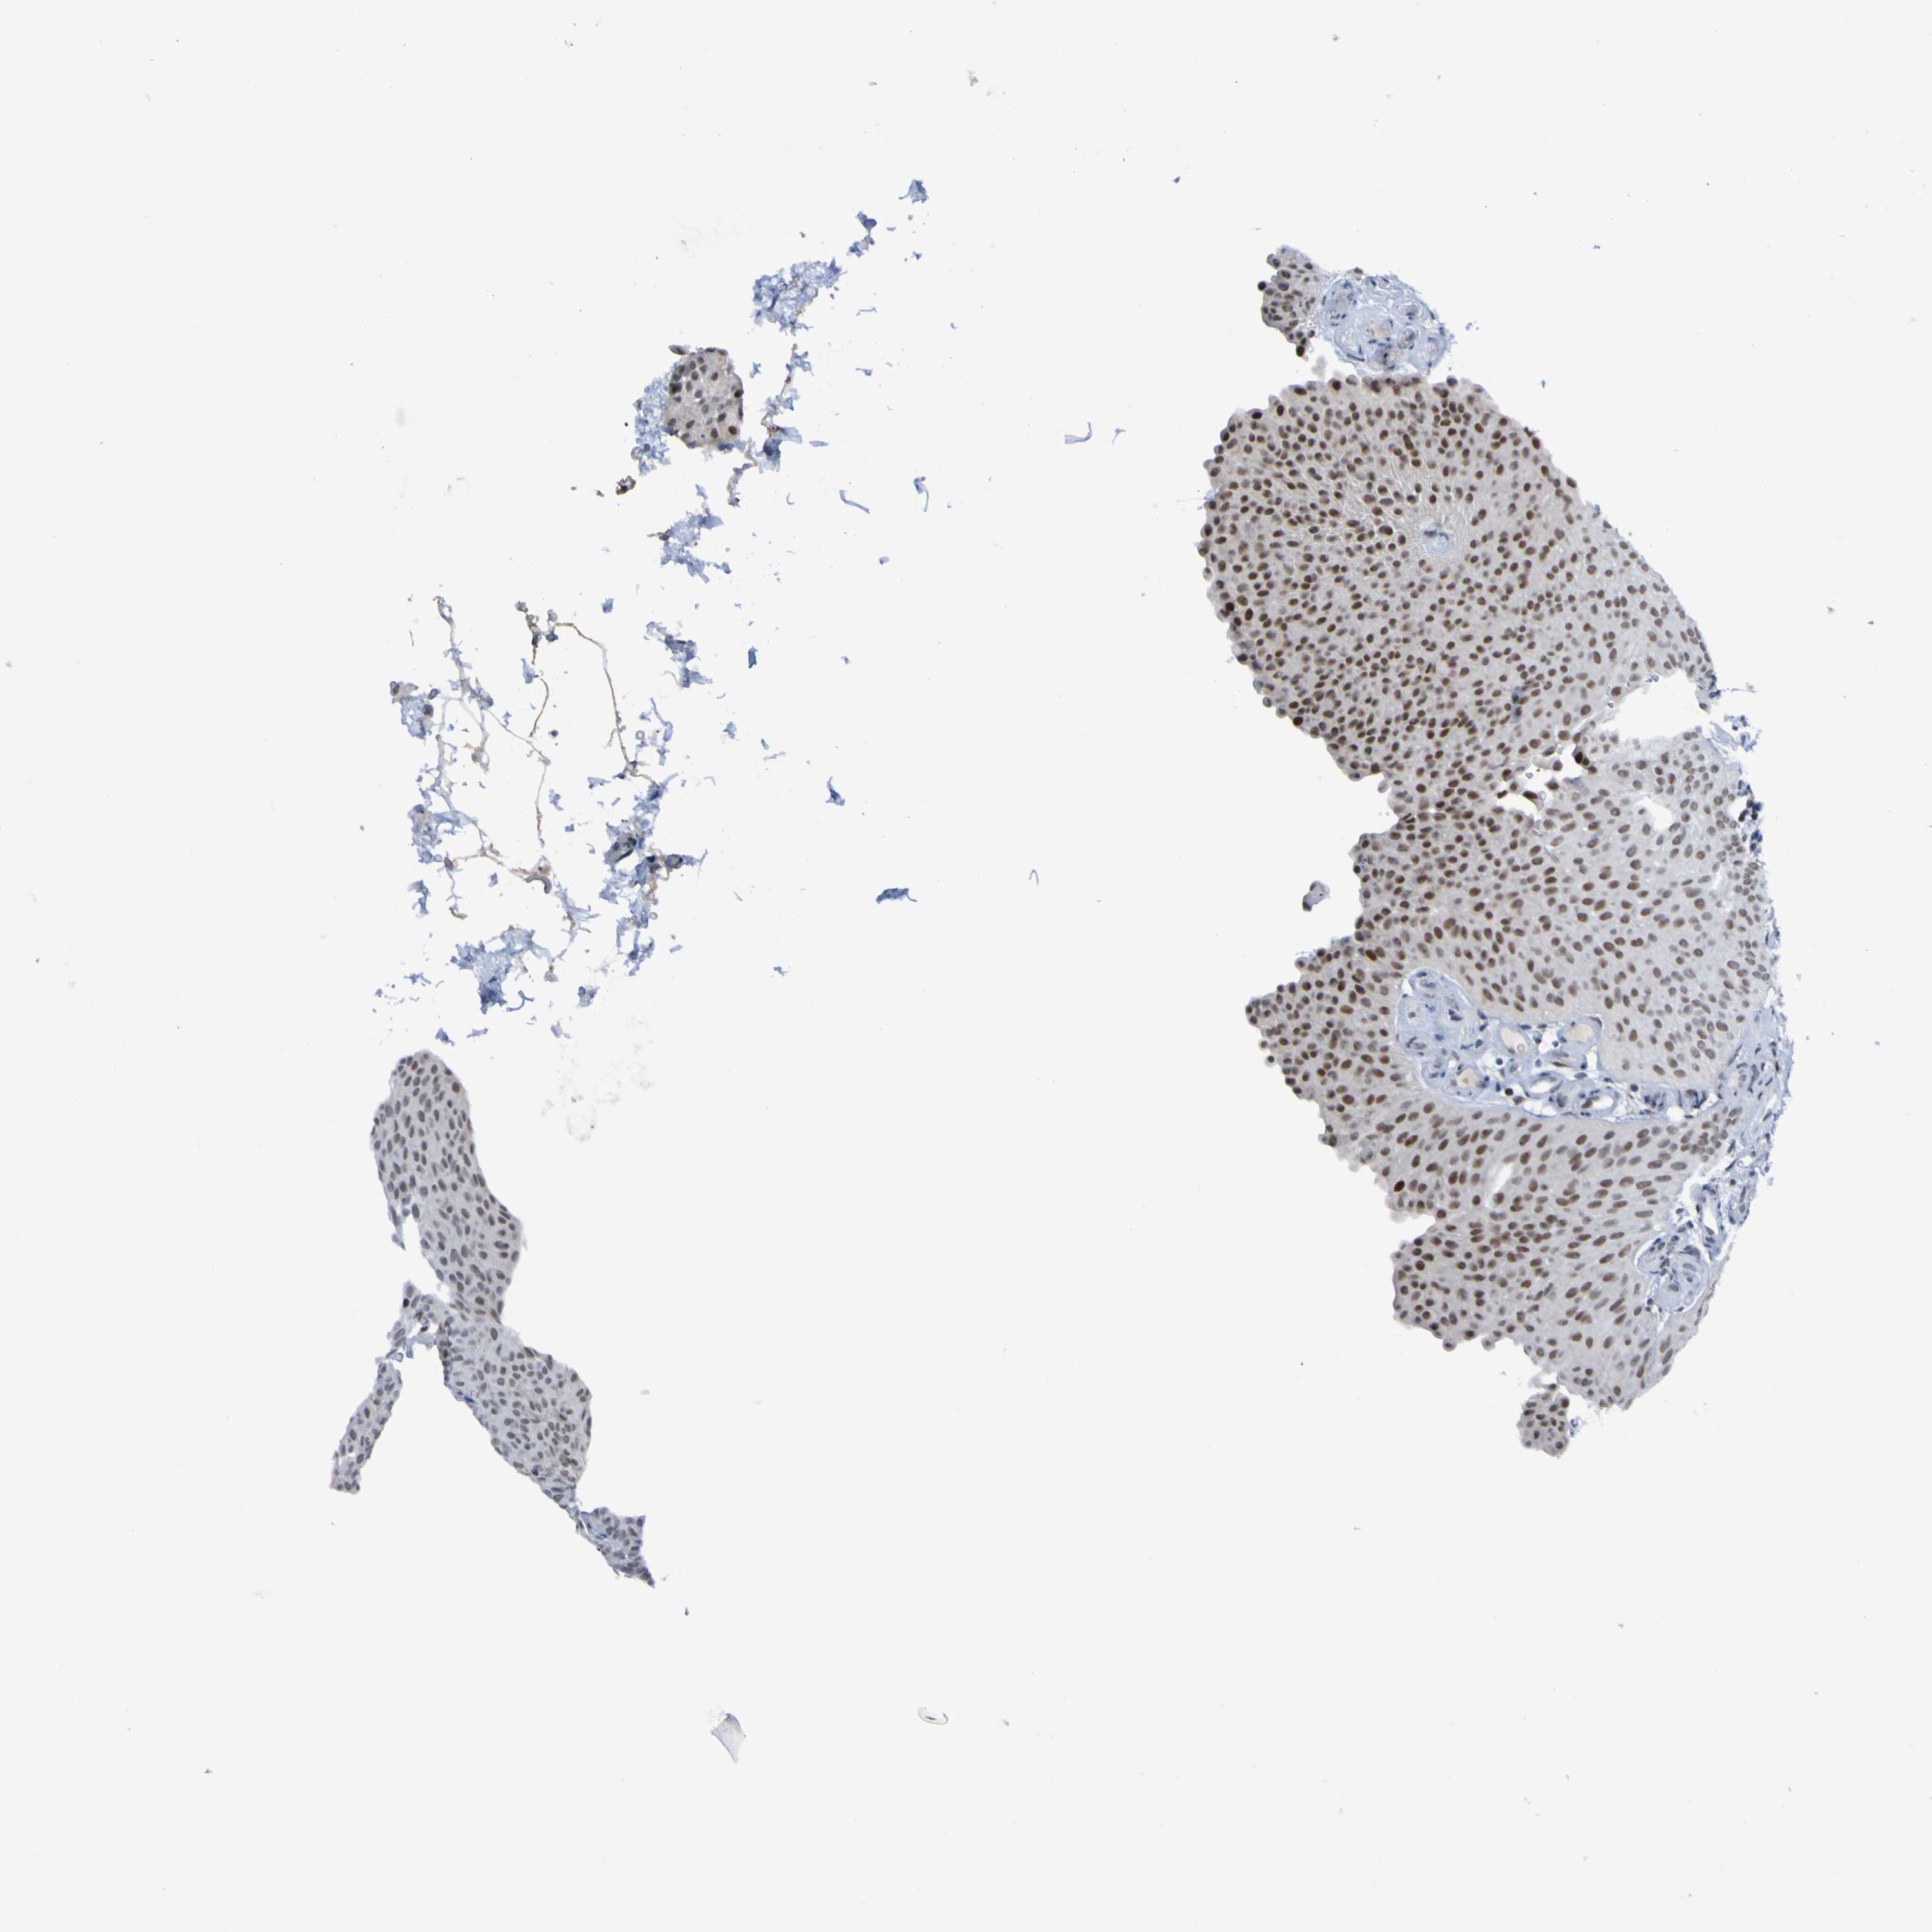

UROTHELIAL CANCER - Protein expressioni

A mouse-over function shows sample information and annotation data. Click on an image to view it in a full screen mode. Samples can be filtered based on level of antibody staining by selecting one or several of the following categories: high, medium, low and not detected. The assay and annotation is described here.

Note that samples used for immunohistochemistry by the Human Protein Atlas do not correspond to samples in the TCGA dataset.

Antibody stainingi

Antibody staining in the annotated cell types in the current human tissue is reported as not detected, low, medium, or high, based on conventional immunohistochemistry profiling in selected tissues. This score is based on the combination of the staining intensity and fraction of stained cells.

Each image is clickable and will lead to virtual microscopy that enables deeper exploration of all samples and also displays staining intensity scores, fraction scores and subcellular localization as well as patient and tissue information for each sample.

Antibody HPA011356

Staining

High

Medium

Low

Not detected

Intensity

Strong

Moderate

Weak

Negative

Quantity

>75%

75%-25%

<25%

None

Location

Nuclear

Cytoplasmic/membranous

Cytoplasmic/membranous,nuclear

Urothelial carcinoma, Low grade

Urothelial carcinoma, High grade